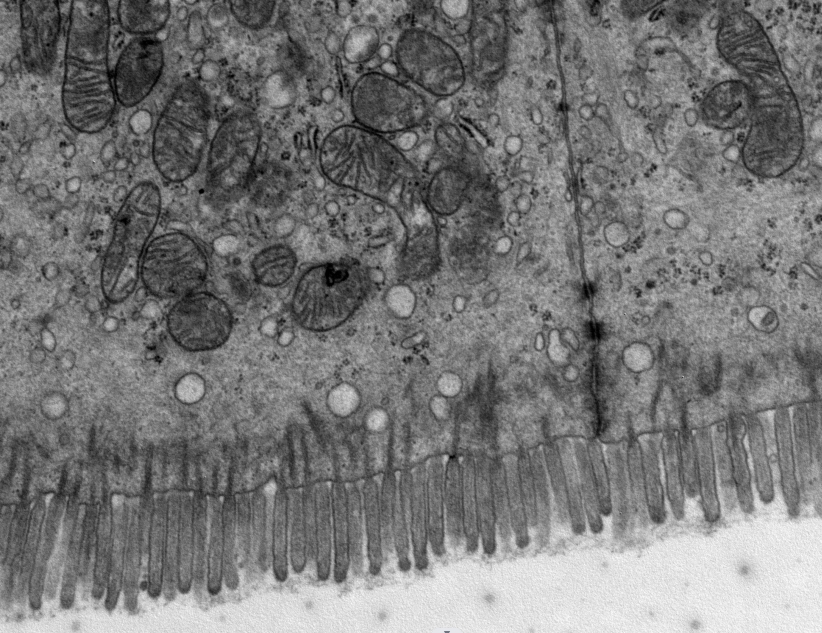

透射电镜(TEM),全称透射电子显微镜,是把经加速和聚集的电子束投射到超薄切片的样品上(通常70-90nm),电子与样品中的原子碰撞而改变方向,从而产生立体角散射。散射角的大小与样品的密度、厚度相关,因此可以形成明暗不同的影像,影像将在放大、聚焦后在成像器件上显示出来。是一种高分辨率(0.1nm-0.2nm)、高放大倍数(0.2K-600K)的显微镜。是观察和研究物质超微结构的强有力工具。透射电镜在细胞生物学、组织学、病毒学、病理学、分子生物学、材料科学等诸多领域具有广泛应用。可以观测动物植物细胞超微结构,如线粒体、内质网、高尔基体、溶酶体、叶绿体、液泡、细胞内生细菌等结构及病理变化。可以观测病毒颗粒、外泌体、病原微生物、各类细菌真菌、纳米材料及纳米颗粒、晶体结构。